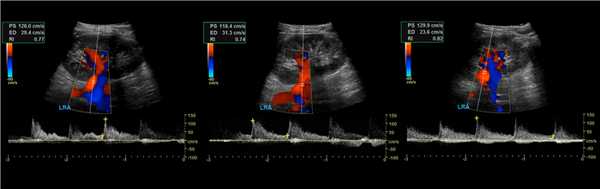

Почечную артерию следует оценивать в семи точках: при выходе из аорты, в проксимальном, среднем и дистальном сегментах, а так же верхушечную, среднюю и нижнюю сегментарные артерии. Оцениваем пиковую систолическую (PSV) и конечно-диастолическую (EDV) скорости кровотока, индекс резистивности (RI), время ускорения (АТ), индекс ускорения (PSV/АТ). Подробнее смотри Доплер сосудов.

Нормальный спектр почечных артерий имеет выраженный систолический пик с антеградным диастолическим потоком на протяжении всего сердечного цикла. У взрослых в норме на главной почечной артерии PSV 100±20 см/сек, EDV — 25-50 см/сек, у детей раннего возраста PSV 40-90 см/сек. В сегментарных артериях PSV падает до 30 см/сек, в междолевых до 25 см/сек, в дуговых до 15 см/сек и междольковых до 10 см/сек. RI в воротах почки

Рисунок. Нормальный спектр почечных артерий — высокий систолический пик, антеградный диастолический поток, низкое периферическое сопротивление — RI в норме